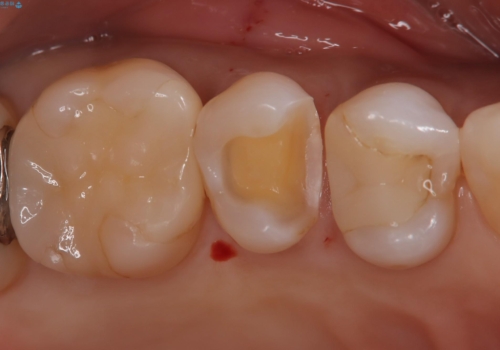

- 他院でいれたセラミックインレーが脱離して、来院されました。

新たに製作を希望されたため、当院で治療しました。

当院でのセラミックインレーの治療は、ラバーダムを使用しています。